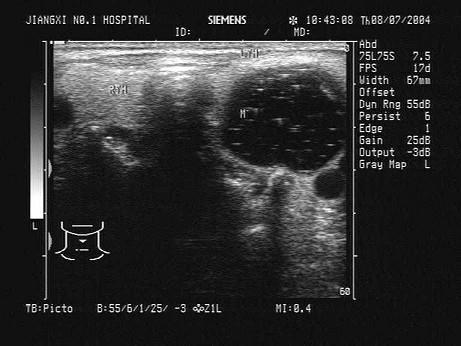

问题 患者,女,25岁,颈部触及肿块半年余,无明显不适。甲状腺超声见右侧甲状腺一单发异常光团,如图。最可能的诊断为?(?)

选项 A.甲状腺癌 B.结节性甲状腺肿 C.甲状腺腺瘤 D.甲状腺炎 E.甲状腺囊肿

答案 C